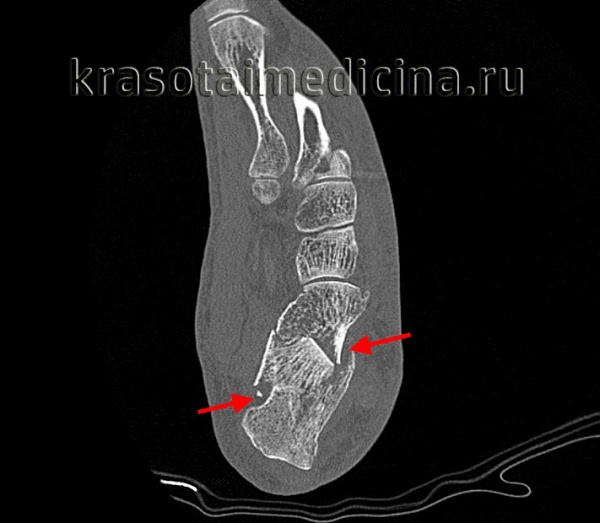

2. Компьютерная томография:

- Исследование выполняется с шагом 1 мм и построением следующих реконструкций:

• Перпендикулярно задней фасетке для визуализаций диастаза или депрессии и обнаружения постоянного фрагмента пяточной кости, включающего опору таранной кости (рис. 3, А-Б)

• Параллельно плоскости пола для получения срезов, перпендикулярных пяточно-кубовидному суставу (рис. 3, В)

• В сагиттальной плоскости для оценки ориентации фрагментов перелома задней фасетки (рис. 3, Г)